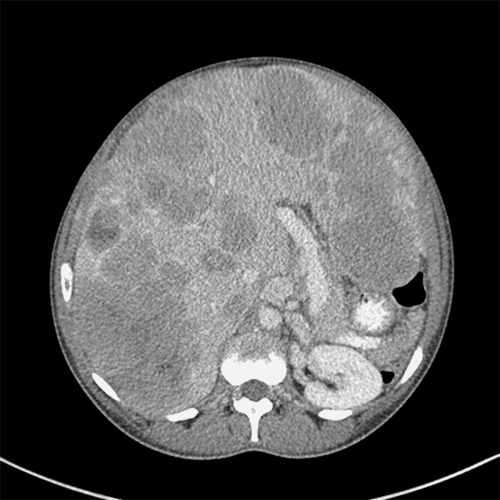

Fortunately, a potential living liver donor was identified. Donor liver MRI revealed acceptable steatosis but unusual biliary anatomy with five bile ducts converging at the confluence. Donor protocol CT demonstrated a Nakamura type D portal vein configuration10 (Figure 2A, 2B). The anterior sector of the donor's liver was supplied by a branch of the left hepatic artery running within the same portal pedicle as the right anterior sector portal vein (Figure 2C, 2D). Estimated volumes of the posterior segment graft (1111 cc) and the donor remnant liver (855 cc) were obtained (Figure 3A, 3B).

Figure 2. Preoperative CT Angiography of Donor Liver. Published with Permission

A and B) Donor portal vein anatomy consistent with a Nakamura type D configuration. C and D) Anterior sector supplied by a branch of the left hepatic artery coursing within the same portal pedicle as the right anterior sector portal vein